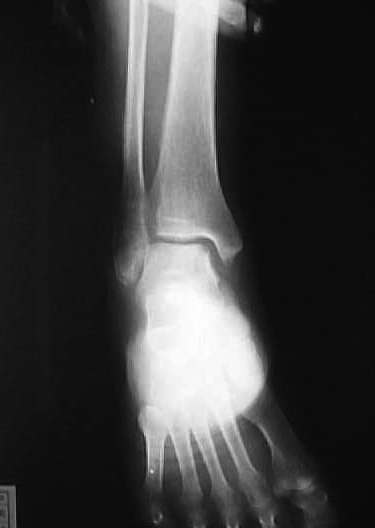

【スライド7】

7 318日 (14日目)

X線撮影依頼。体重の付加を禁止したまま2週間経過。全身症状は良好。X線写真を見て骨折部位の整復・固定状況が不十分と判断、可能な限り正常な位置への復元が出来ないかを検討する。患部を触診し骨癒合が完全に行われていないと判断し、再度徒手整復を行う。中枢骨片がやや前下方に位置すると判断し、仰臥位にて末梢骨片を左手第2指で固定したまま、中枢骨片に左右の母指で前方より後方への圧迫を加え整復する。持続性を保つために生ゴムを用い、母指圧と同様の力が持続するようにテープを用いて固定した後、前日までと同様の固定を行う。